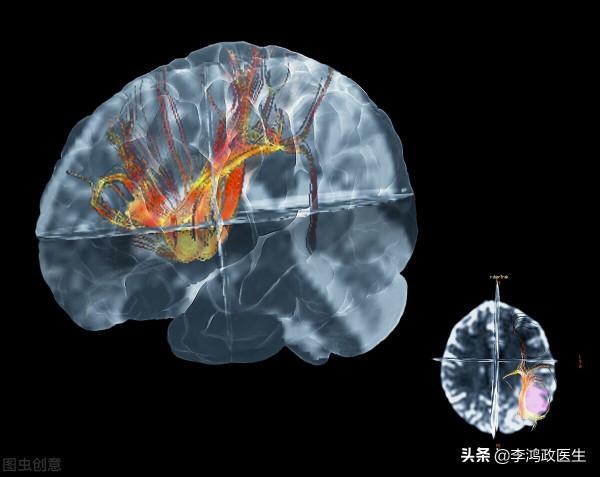

這回看的更清楚了,影像科醫生和神經內科、神經外科醫生坐在了一起,討論了,認為左側顳葉這個東西是個膠質瘤。

大腦最常見的兩種細胞,一種是神經元,一種是神經膠質細胞。神經元是明星,人腦所有的功能都是靠神經元(神經細胞)來完成,我們的記憶、語言、思維等等都是它們在主持。而膠質細胞就比較低調了,它們種類多種多樣,功能也繁複,有些是神經元的醫生,有些是保姆,還有些是保安,總之,膠質瘤細胞發揮了很大的作用。

醫生說總體還是很順利,估計是切乾淨了,術中快速病理活檢提示的確是膠質瘤,而且是瀰漫性星型細胞瘤。

術後病理活檢結果也回報了,是個II級的。醫生說。

醫生後來告訴高小姐,之前一直說聞到有臭水溝的味道,可能是幻嗅,不一定是真的有鼻竇炎引起的。顳葉這裡有嗅覺中樞,受損後可能出現幻嗅,聞到一些不存在的味道。